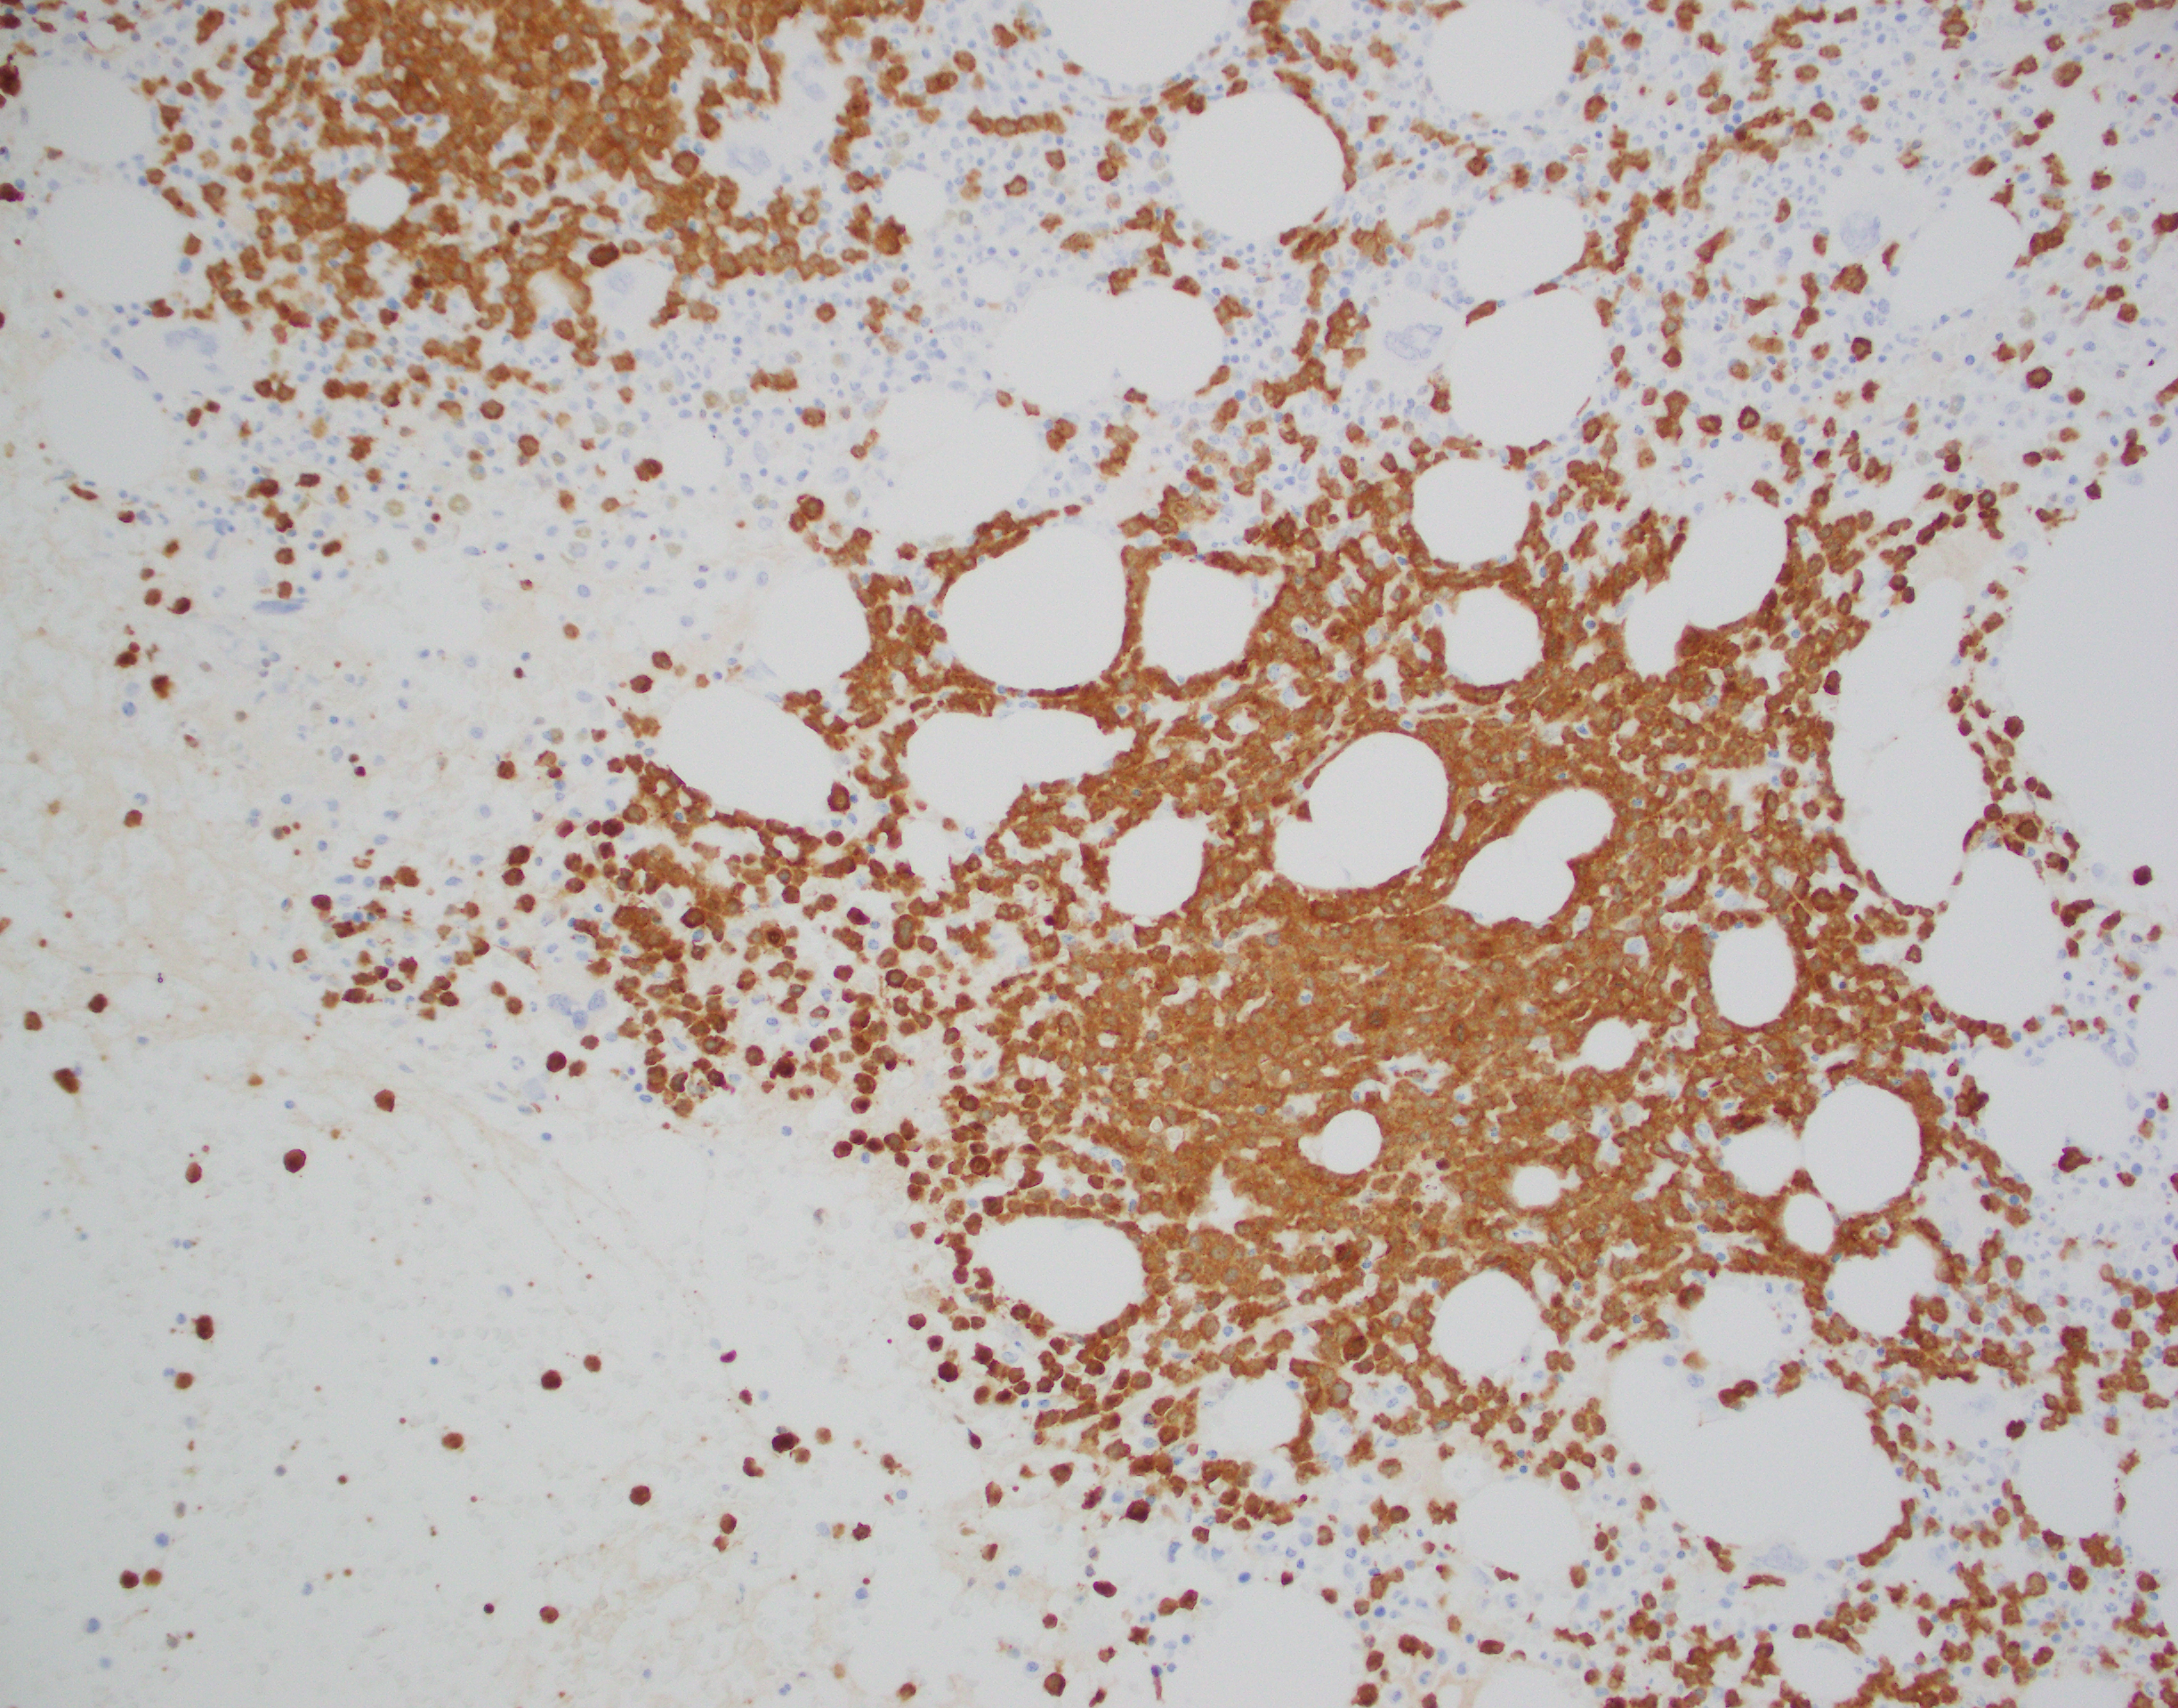

The immunophenotype for APL is quite distinct and characterized by low or absent expression of CD34 and HLA-DR (in keeping with the cellular differentiation from blast to promyelocyte). APL cells are positive CD33 and CD13 with most cases showing expression of CD117 (sometimes weak). APL cells are usually negative for CD15, CD65, CD11a, CD11b, and CD18. The microgranular variant may display positive staining for CD34 and CD2. For both variants, IHC with antibodies to the PML gene demonstrates a nuclear multi granular pattern with nucleolar exclusion, a finding that is unique to APL and not seen in AML or normal promyelocyte morphology.